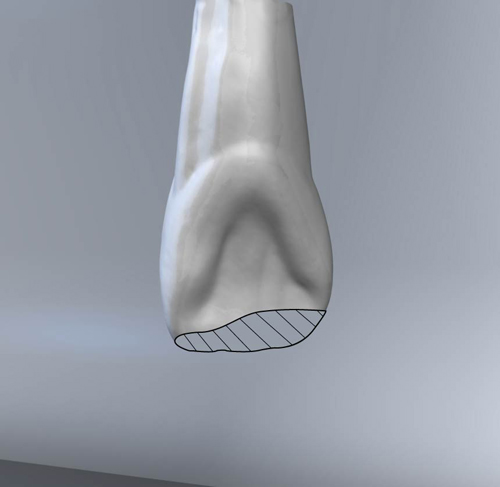

En ciertas áreas del saber humano, el lenguaje confuso o criptográfico Muchas son las técnicas elaboradas para lograr un desgaste selectivo, y numerosos autores han expuesto en su momento variadas formas de lograr una función oclusal fisiológica mediante el ajuste de la misma. Han pasado años desde entonces y, sin embargo, aún hoy, un altísimo porcentaje de profesionales “navega” por el mar de la confusión oclusal, dada la diversidad de conceptos y escuelas, sin lograr arribar a costa alguna donde poder anclar un conocimiento sólido sobre cómo tratar la oclusión Ya se esté realizando una simple obturación, endodoncia, incrustación, radectomía u ortodoncia, la lógica pocas veces, en la mayoría de los casos, vincula un tratamiento con otro, siendo el resultado final el mismo caos inicial; enmascarado por mucho tratamiento profesional. El ajuste oclusal es un medio inicial de proveer al sistema enfermo de: Dicha técnica, que puede ser terapéutica en sí misma; consta de dos etapas, a saber: 1) Ajuste Oclusal por Adición Mediante el estudio de la guía anterior, encargada de efectuar las Disclusiones durante las excursiones mandibulares, podremos observar si ésta es funcional o no. • Marcas de carácter continuo, si en ese recorrido se produce la Disclusión de los sectores posteriores y todo marcha correctamente. FIG 1-2 Si por el contrario observamos: • Marcas de carácter discontinuo, significa que dicha Disclusión se está efectuando por medio de una pieza dentaria posterior a la guía anterior. FIG 3-4-5 (FIGS. 3, 4 Y 5). En la figura 6 las flechas indican, en un caso clínico de análisis oclusal, la presencia de marcas discontinuas que indican Interferencias en Propulsiva. FIG 6-7 Y por último, si existieran: • Abrasiones de las áreas discluyentes en las áreas de diagnóstico de la guía anterior, deberemos aportar material a dicha zona para no permitir el choque lateral de las piezas posteriores (Ajuste Oclusal por Adición) En las imágenes 11 y 12 podemos observar la adición de composite en la punta de un canino derecho, previa la observación de la Faceta Parafuncional remarcada durante el análisis oclusal en el articulador. (FIGS. 8 A 12). 2) Ajuste oclusal por Sustracción o Desgaste Habiendo cumplido ya con la verificación de la funcionalidad de la Guía Anterior, comenzamos los desgastes en céntrica, a fin de lograr un único arco de cierre, guiado eficazmente por la Guía Anterior; es decir: la coincidencia entre Oclusión Habitual y Oclusión en Relación Céntrica. En este caso, intentar gastar dichos puntos, de ser posible sólo en las cúspides de corte o no fundamentales: • Crestas Triangulares Internas, Cúspides Vestíbulares Superiores • y un poco de las Crestas Triangulares Internas, Cúspides (FIGS. 13 A 16). Si la deflección es hacia el lado opuesto, se invierten los desgastes. En las migraciones hacia adelante, las únicas razones posibles están en los puntos estabilizadores (FIG. 17); es decir: -Vertientes Distales de los Rebordes Marginales, Triangulares (FIG 17) (FIG 18 A-B-C-D) Obsérvese cómo, en una boca prácticamente entera, comienzan a “desmoronarse” prismas adamantinos (FIG. 19), como consecuencia de un punto prematuro de contacto, ubicado en la posición de un estabilizador, que provoca la discrepancia horizontal postero-anterior causante de dicho efecto (FIG. 20). FIG 19-20 Dicho punto, será necesario ajustarlo antes de cualquier tratamiento en la zona ¿Cuáles serían las consecuencias si esos incisivos fueran implantados tal como es frecuente observar en múltiples congresos y cursos de implantología, donde el tema de la oclusión no es más que un cuadro polifacético y anecdótico? 14 15 16 17 Todo producto del adelantamiento mandibular Realizados ya los desgastes en céntrica, obteniendo de esta manera un único arco de cierre, es decir, oclusión en relación céntrica, debemos realizar el ajuste de las excéntricas, apoyando la acción de la guía anterior, para lo FIG 22 a. De un lado a otro de un mismo maxilar, la imagen es especular, o sea invertida. b. En hemimaxilares cruzados, la imagen es idéntica. Allí donde existan colisiones entre cúspides, se deberá crear un surco para que dicha cúspide antagonista migre a su través, tanto en el lado de no trabajo, como en el de trabajo y en el de propulsión. FIG 23 Es importante conservar esta parte del surco, ya que si no existieran, los contactos entre cúspides serían en superficie y no puntiformes (fig. 24). FIG 24 1. Obtener un único arco de cierre con coincidencia entre oclusión habitual y relación céntrica. 2. El cierre mandibular debe ser recibido sólo por la tabla premolar-molar. 3. Durante las excursiones funcionales es la guía anterior la que debe sufrir las fuerzas laterales. 4. De cumplirse estas dos premisas debemos obtener libertad de desplazamiento (no confundir con libertad en céntrica) a las piezas posteriores mediante la creación de surcos disclusivos. Examinadas ya las posibles migraciones mandibulares y los desgastes o aposiciones necesarios para poder ocluir en céntrica, es fundamental recordar que, previamente a todo tipo de ajuste, se ha hecho necesario ubicar a la mandíbula en relación céntrica. Para ello debemos utilizar el propio funcionalismo muscular 22 FIG 25 Y esto no significa otra cosa que: piezas dentarias estables en todos los planos del espacio, ATM centrada en la cavidad glenoidea, periodontos sin tensión, músculos en la dimensión de elongación adecuada para un fisiologismo Paz absoluta en la intimidad del Sistema Estomatognático. Y así, como corolario final, es posible establecer una regla de oro similar en importancia a la conocida formula: Forma = Función Ésta es: FIG 26 FUNDAMENTOS NEUROFISIOLÓGICOS DEL REGISTRO DE OCLUSIÓN EN RELACIÓN CÉNTRICA ( ORC) MEDIANTE EL USO DE LAMINILLAS DE LONG CUADRO